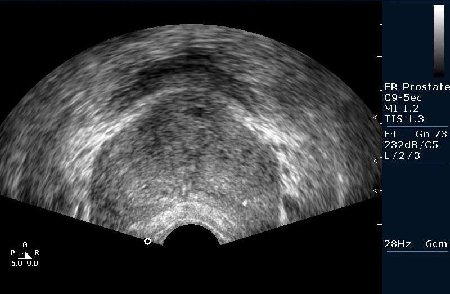

Биопсия предстательной железы под контролем Ультразвуковой визуализации. Рутинная практика в нашем отделении pадиологии, выполняется практически всем пациентам с повышенным уровнем ПСА (естественно, учитывая результаты осмотра урологов).

Биопсийная игла в железе (трепан биопсия)